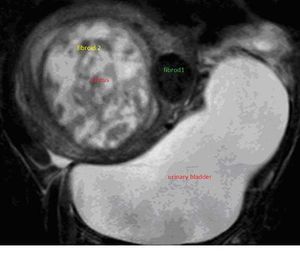

Case History: A 40-year-old female referred for evaluation of lower abdominal pain and polymenorrhea for six months.